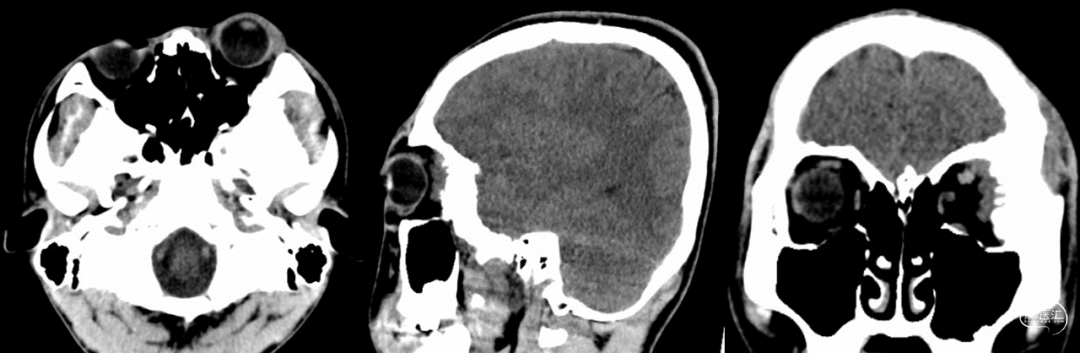

头颅CT组织窗(左侧眼球突出,左侧额颞蝶眶颧骨质增厚)

头颅CT骨窗(显示左侧额颞蝶眶颧骨质增生明显,部分骨质破坏)